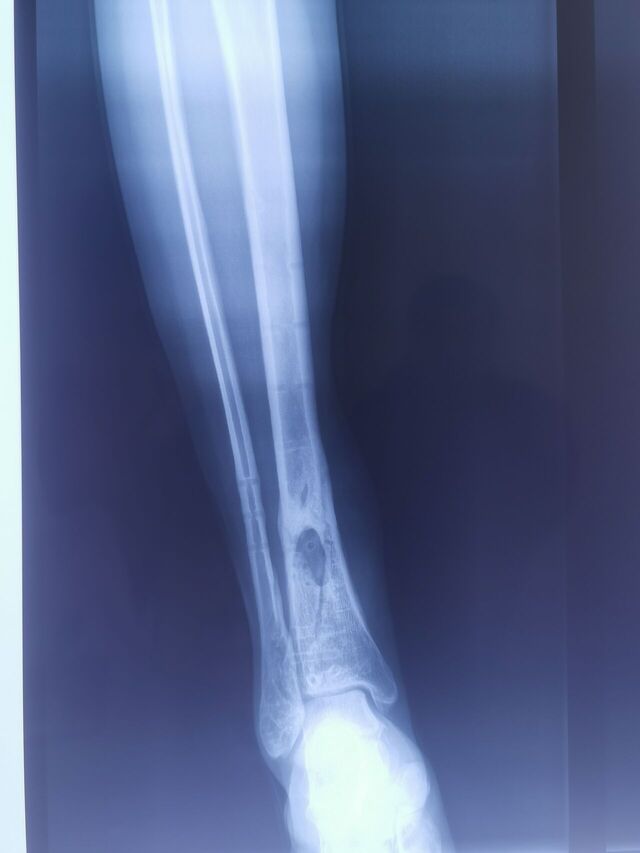

胫后动脉穿支皮瓣术后2个月